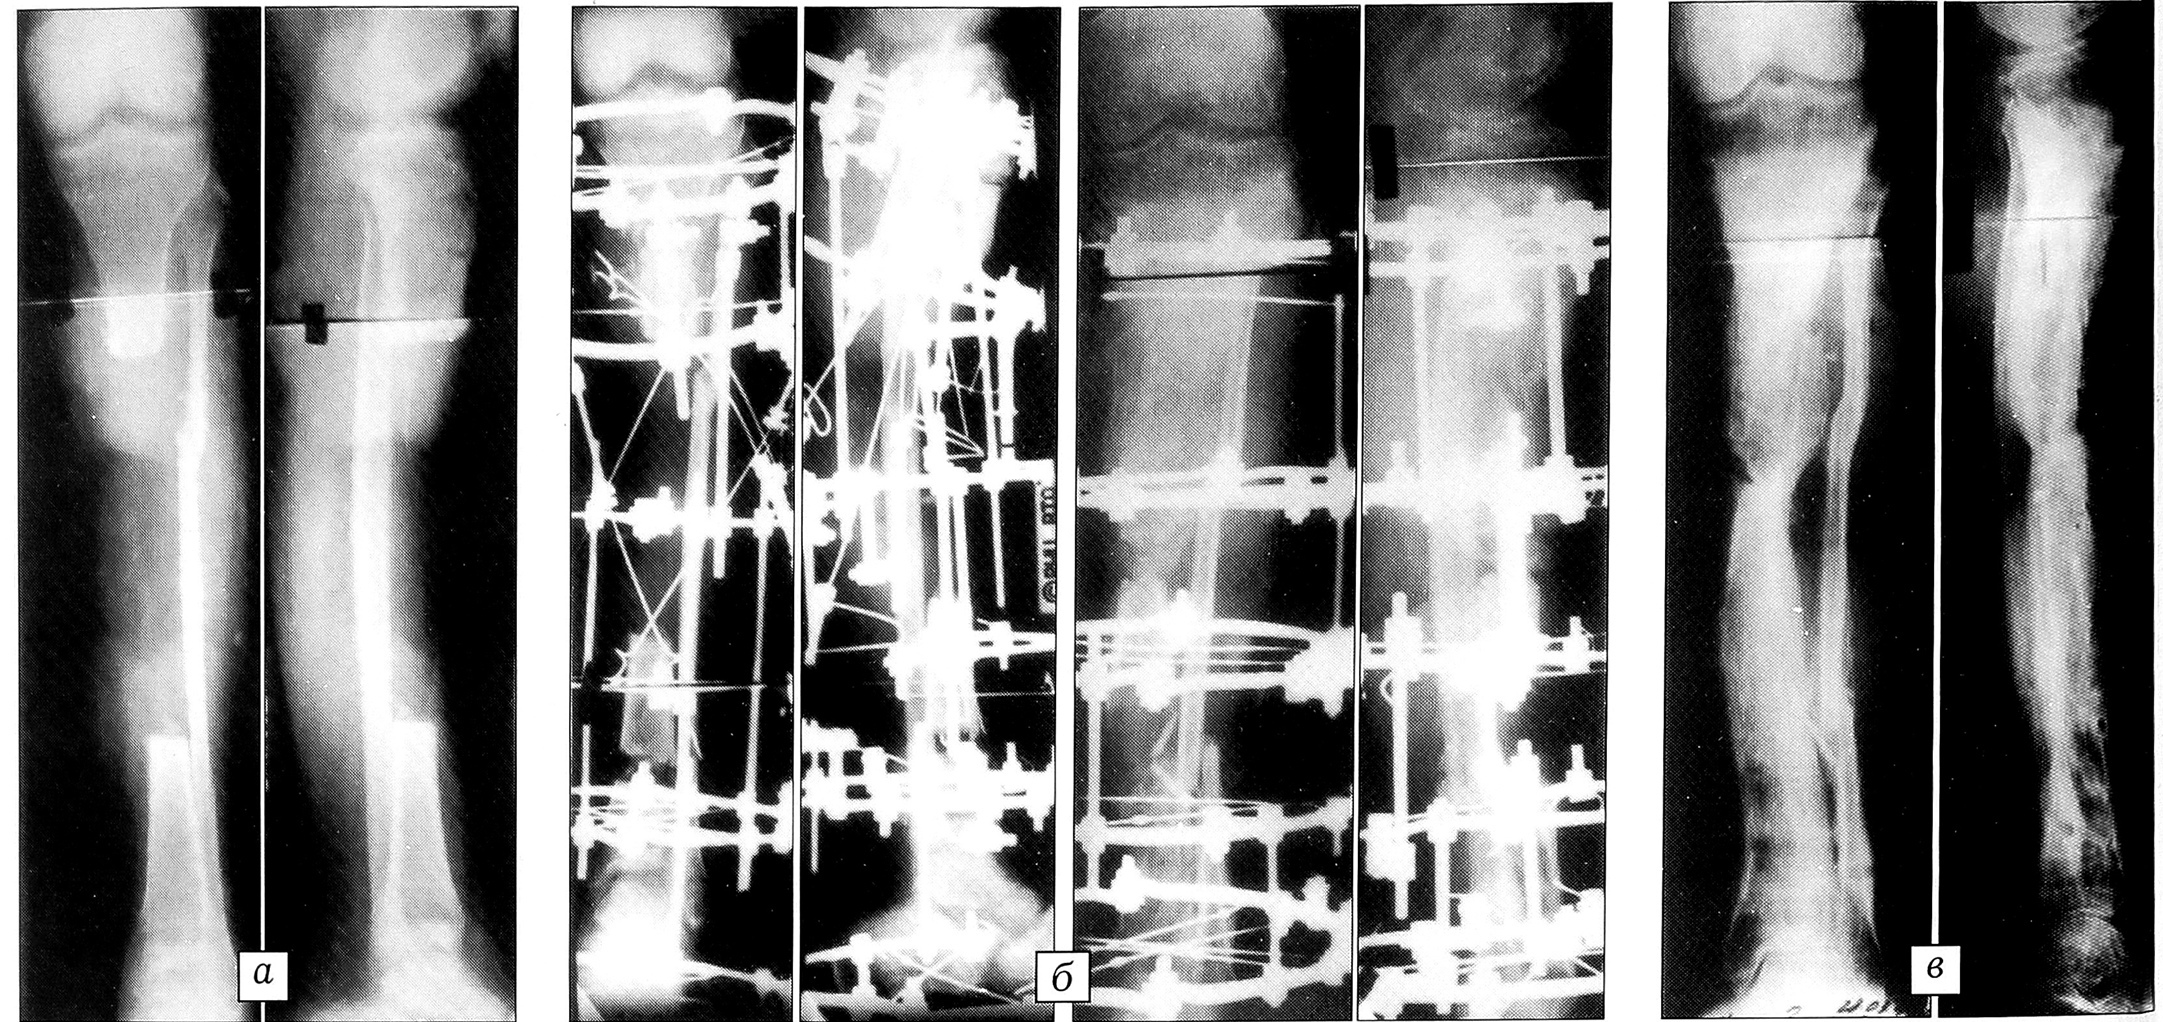

Рис. 1. Рентгенограммы больного Р. 5 лет.a — до лечения; б — в процессе остеосинтеза; в — ближайший результат лечения; г — результат лечения через 3,5 года после снятия аппарата.

Больной Р.,5 лет, поступил на лечение с диагнозом: врожденный ложный сустав костей левой голени; укорочение конечности 6 см; дефект большеберцовой кости (с учетом необходимости оперативного взаимопогружения истонченных на протяжении концов отломков) 10 см (рис. 1). Целость сегмента восстановлена за счет одноуровневого удлинения проксимального отломка большеберцовой кости и погружения его конца в метафизарный отдел дистального. Сформирован дистракционный регенерат величиной 5 см. Дистракция продолжалась 69 дней, фиксация — 116 дней. При контрольном осмотре через 3,5 года целость большеберцовой кости сохраняется.

Рис. 2. Рентгенограммы больной Б. 8 лет.: a — до лечения; б — на этапах остеосинтеза; в — после снятия аппарата.

Больная Б.,8 лет, находилась на лечении по поводу врожденного ложного сустава костей правой голени (рис. 2). Дефект большеберцовой кости с учетом выполненной резекции концов отломков составил 10 см. Дефект полностью замещен за счет последовательного двухуровневого удлинения проксимального отломка большеберцовой кости. Общий срок дистракции — 98 дней. Срок фиксации отломков на стыке — 83 дня.